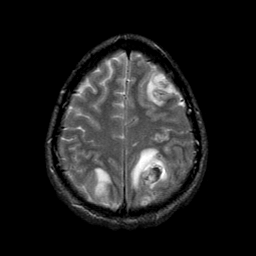

Sarcoma, MR Study #1 mr-t2 -- Slice #19

[Home][Help][Clinical] Slice 19